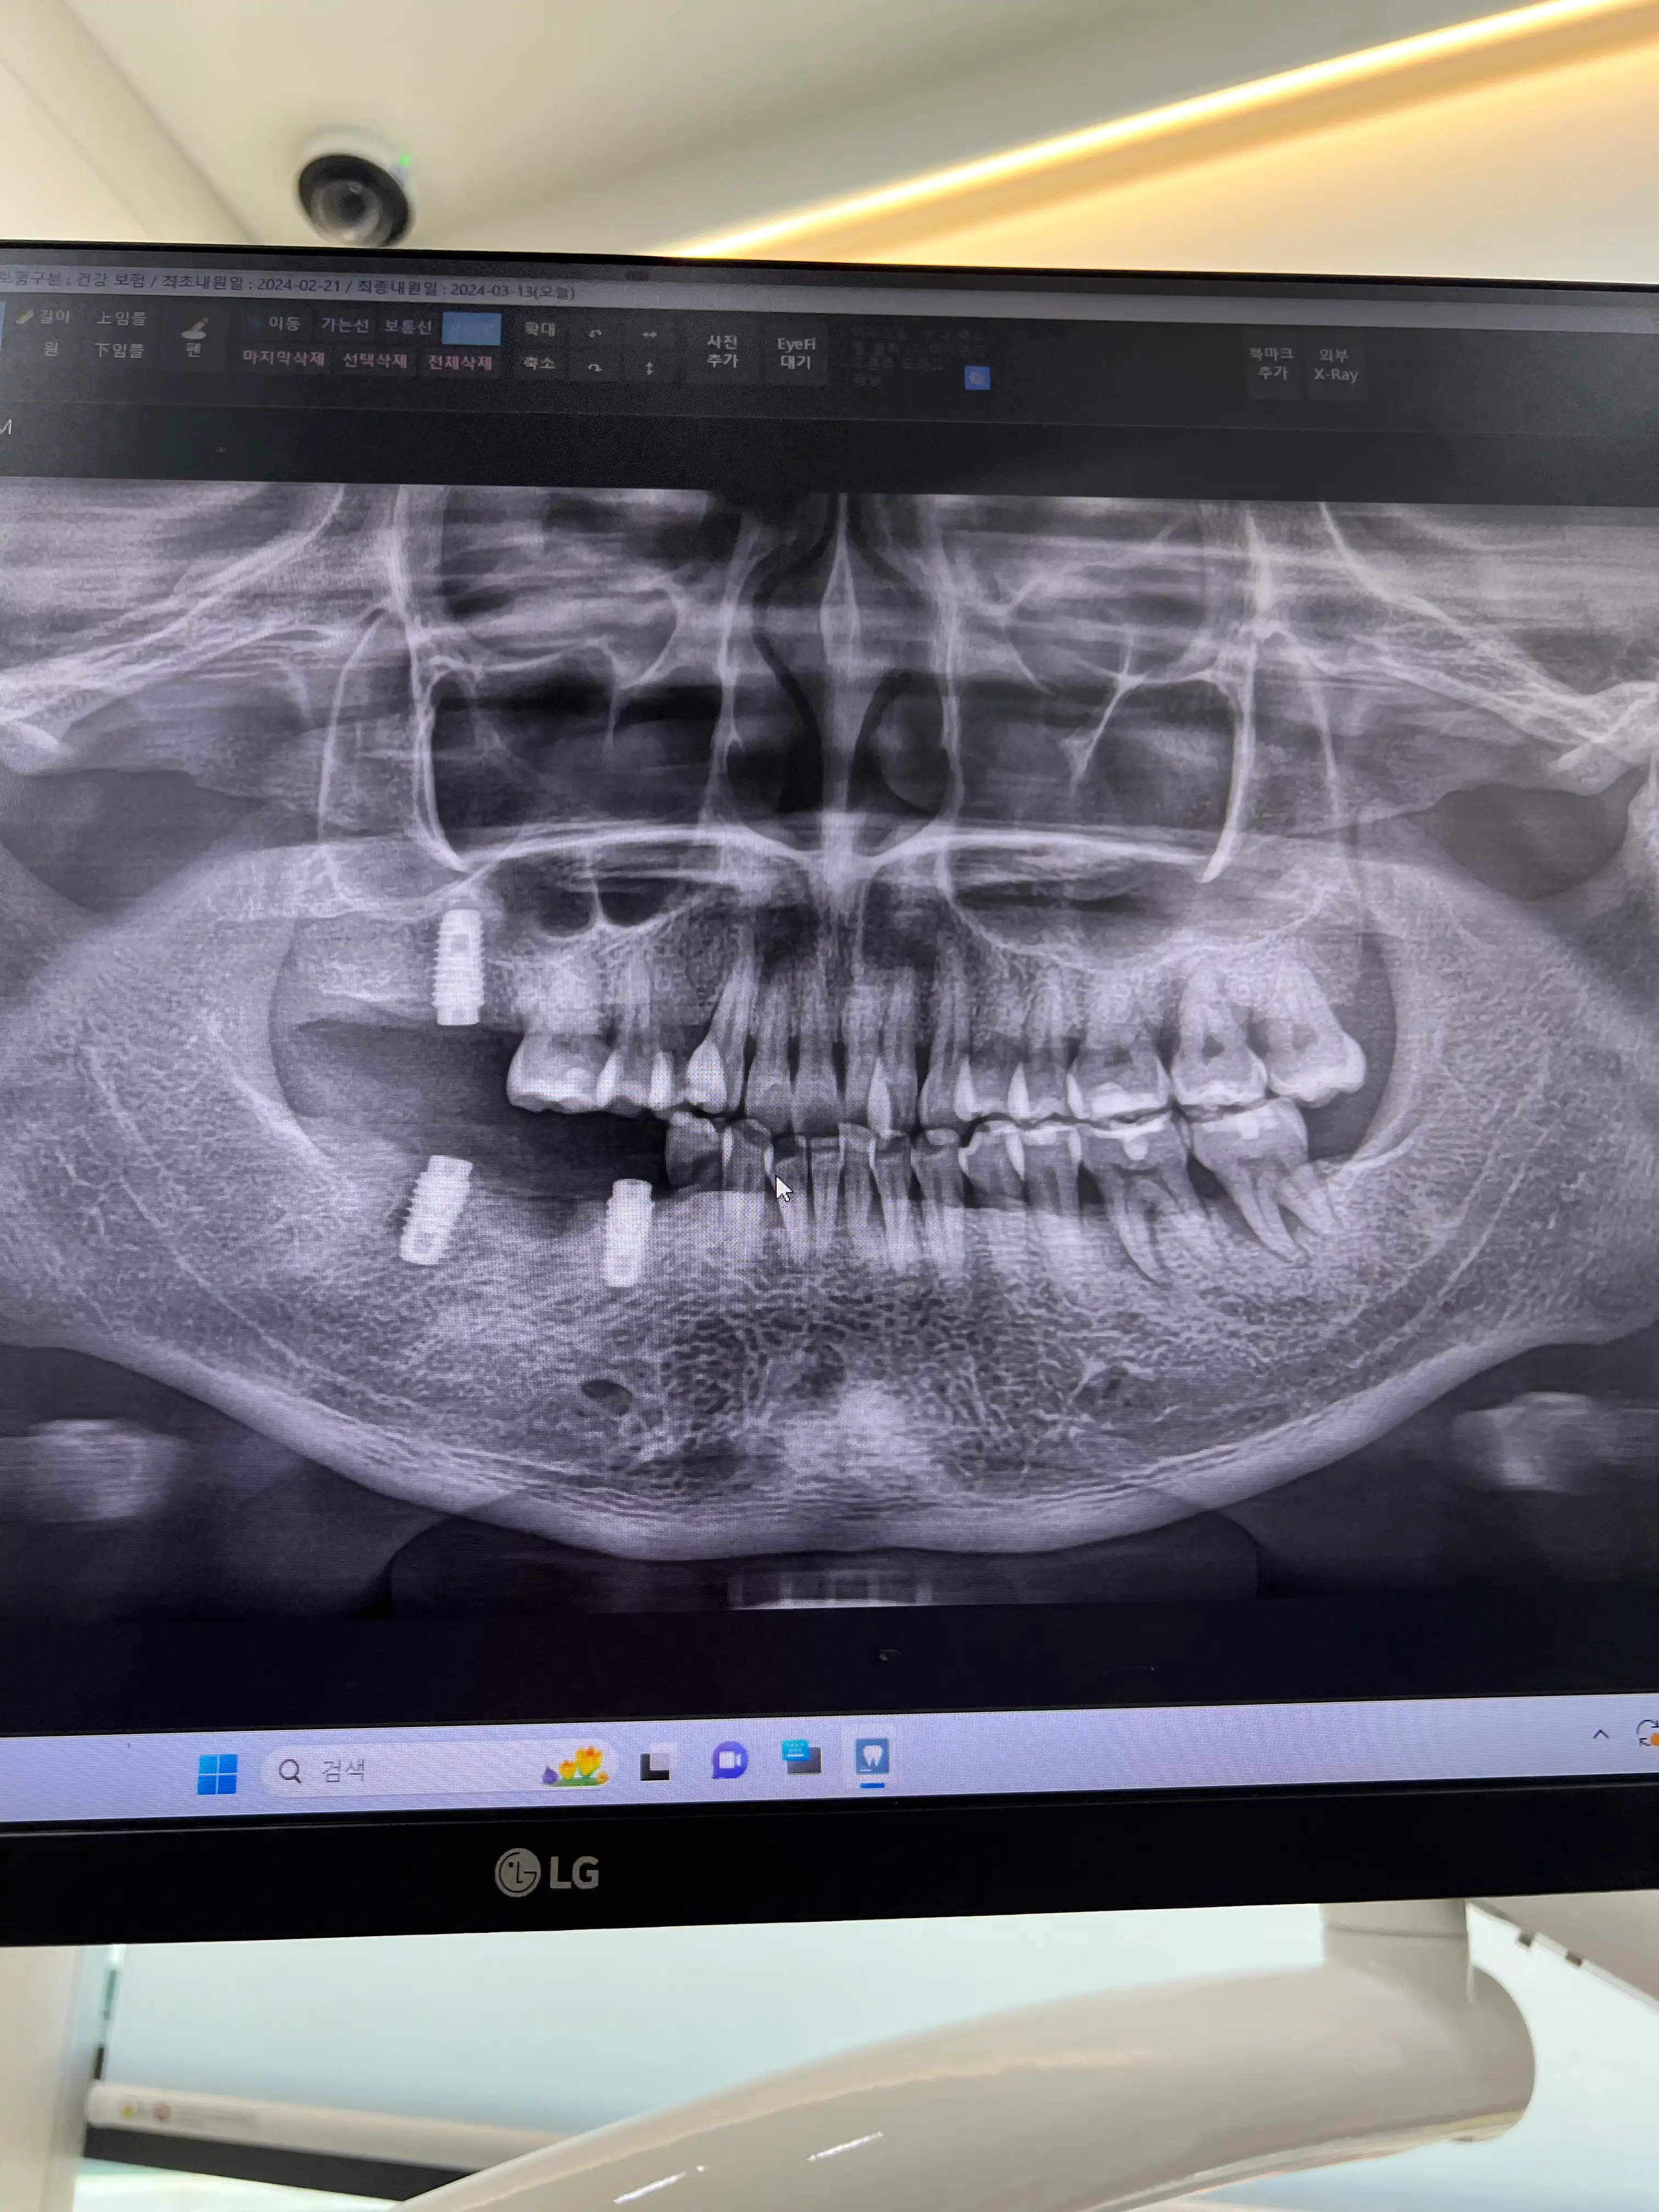

전

상담 잘 받고 왔습니다 깨끗하고 친절하게 잘 상담해 주시더군요, 제 직업이 일정이 들쑥날훅해서 조만간 한가해질 때 진료 시작하러 예약 잡고 가겠습니다 수고하세요~